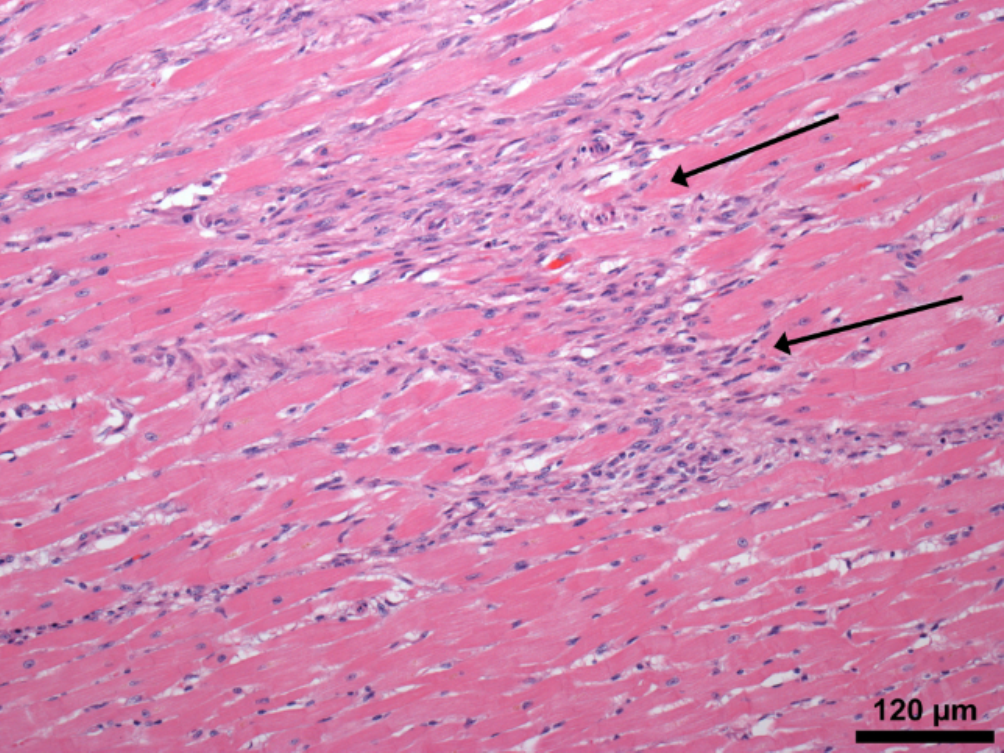

Межуточный миокардит: гистологические исследования

Раздел: Идеи и советы